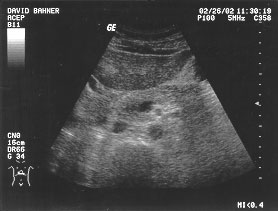

Aorta - renal (unlabeled)